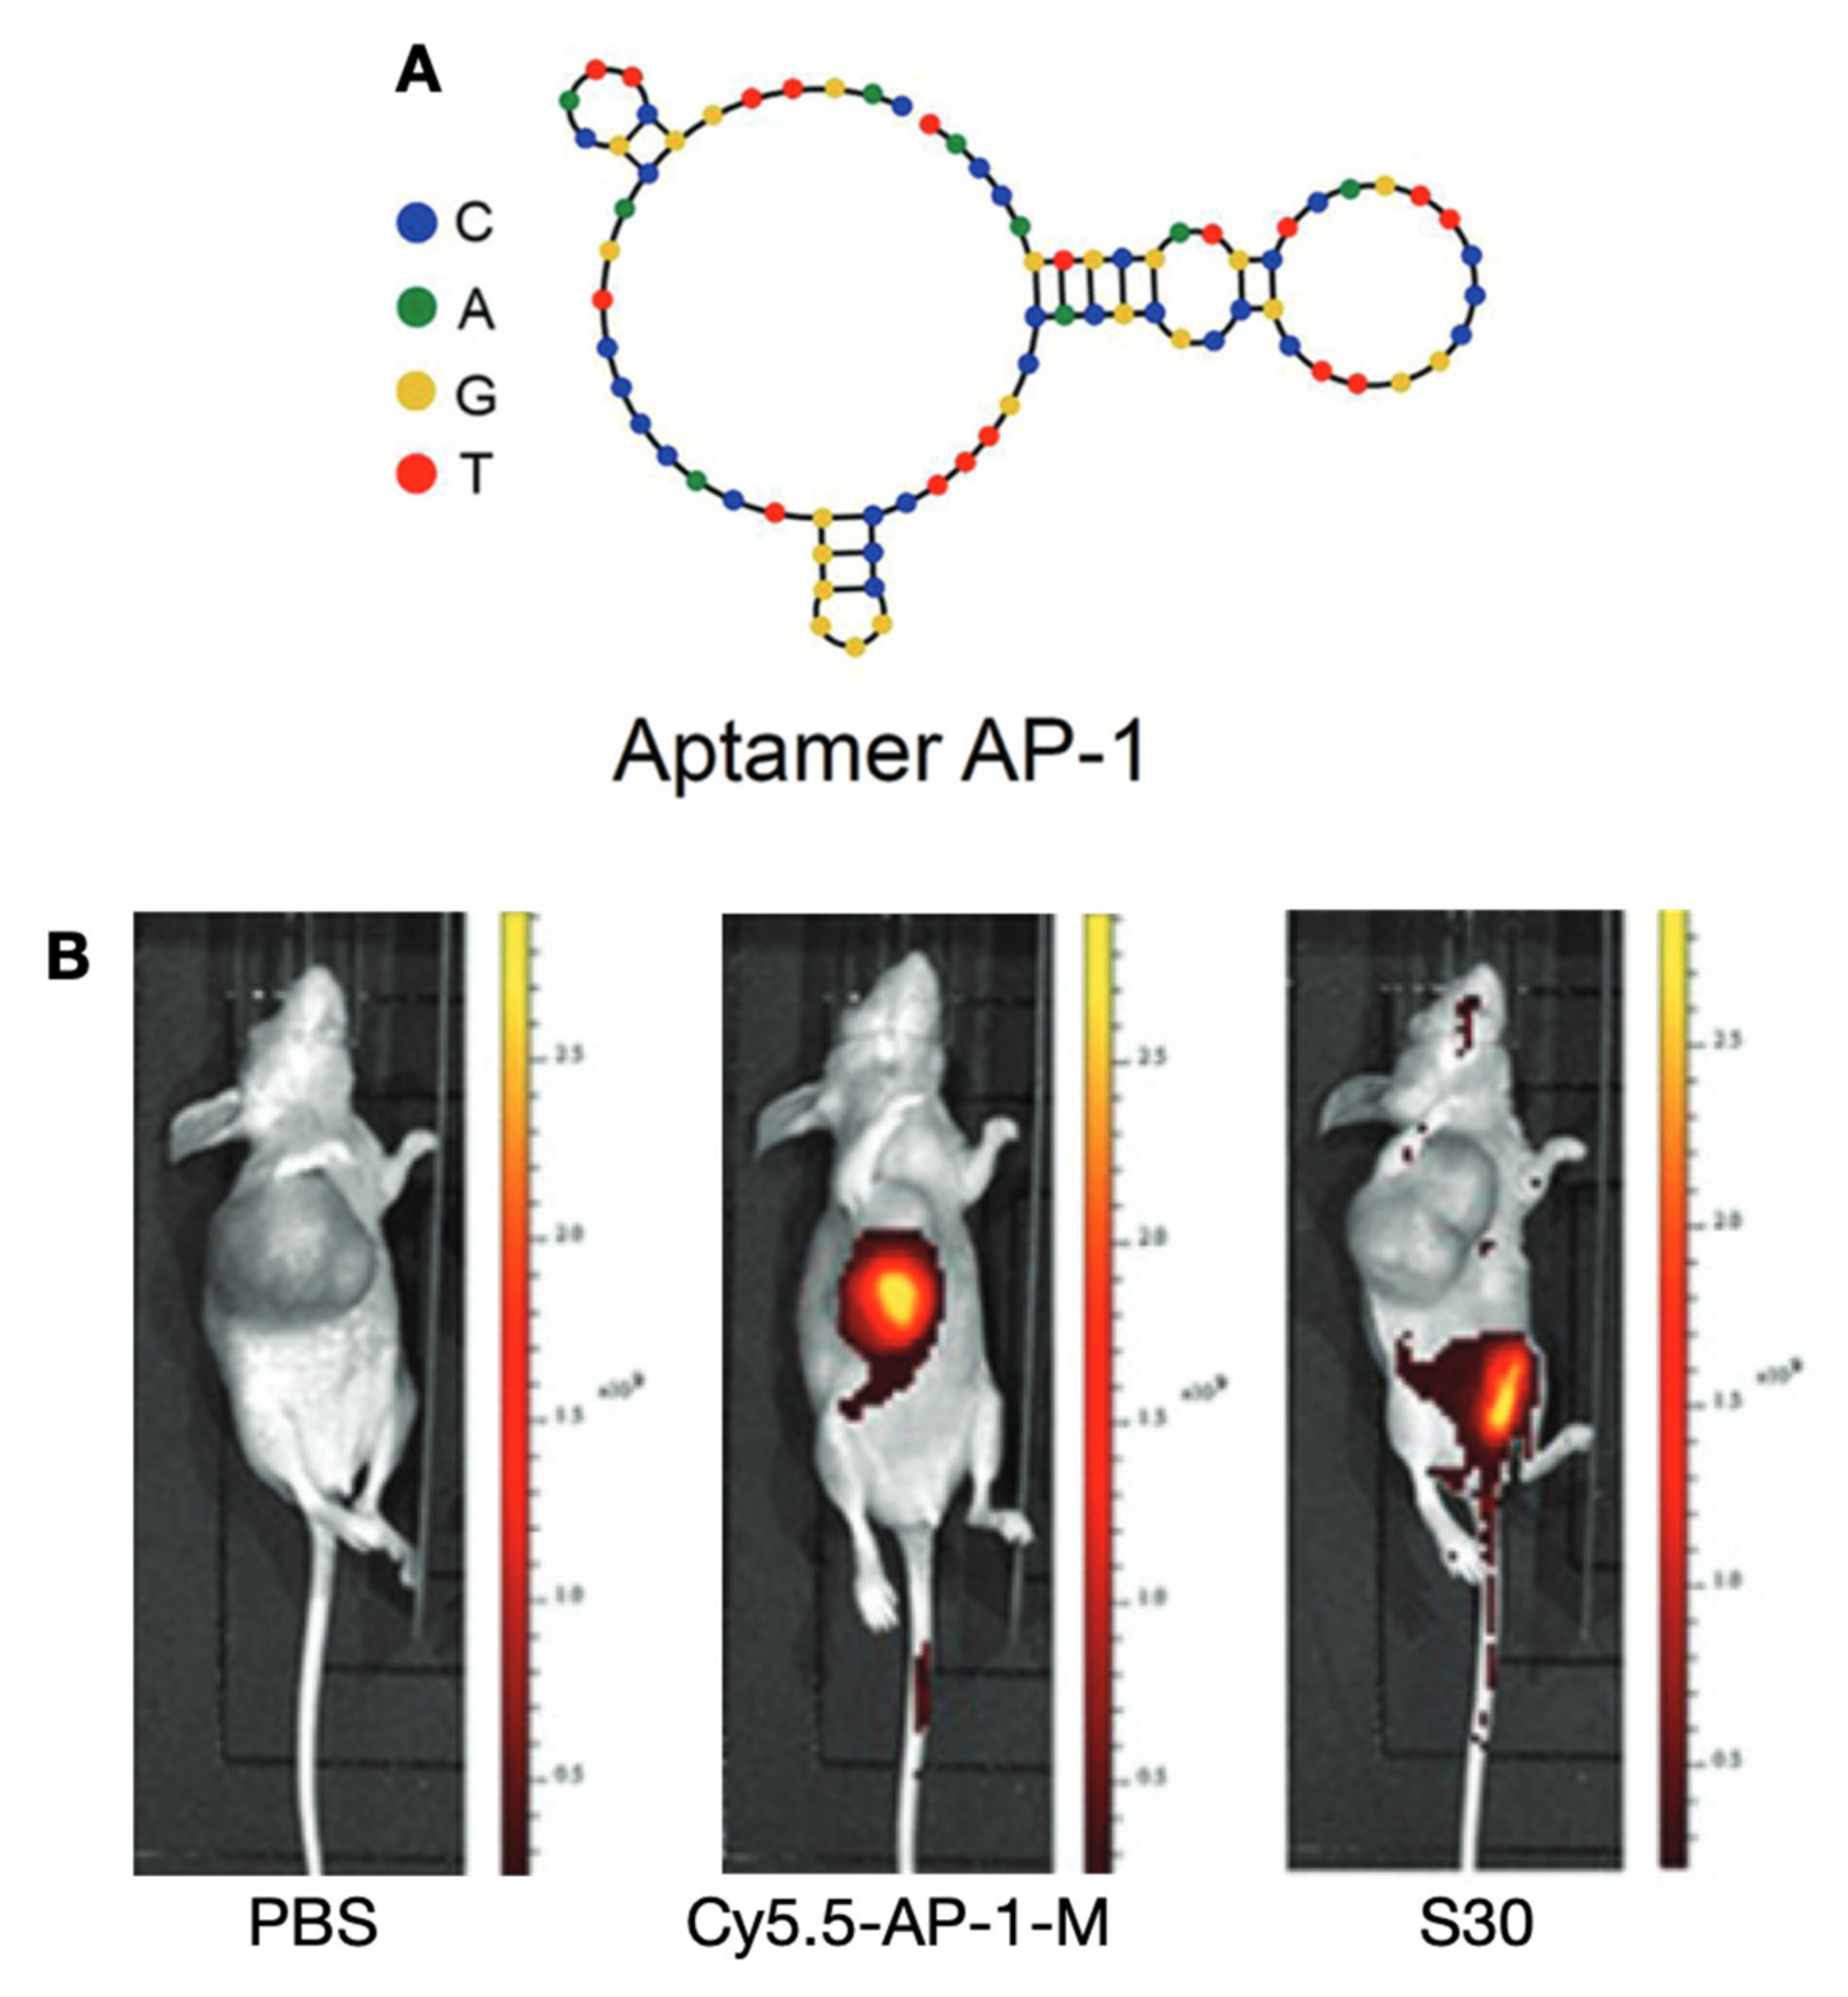

5.1.1. Prominin 1 (PROM1, CD133)-Targeting Probes

- Ge, M.H.; Zhu, X.H.; Shao, Y.M.; Wang, C.; Huang, P.; Wang, Y.; Jiang, Y.; Maimaitiyiming, Y.; Chen, E.; Yang, C.; et al. Synthesis and Characterization of CD133 Targeted Aptamer–Drug Conjugates for Precision Therapy of Anaplastic Thyroid Cancer. Biomater. Sci. 2020. [Google Scholar] [CrossRef]